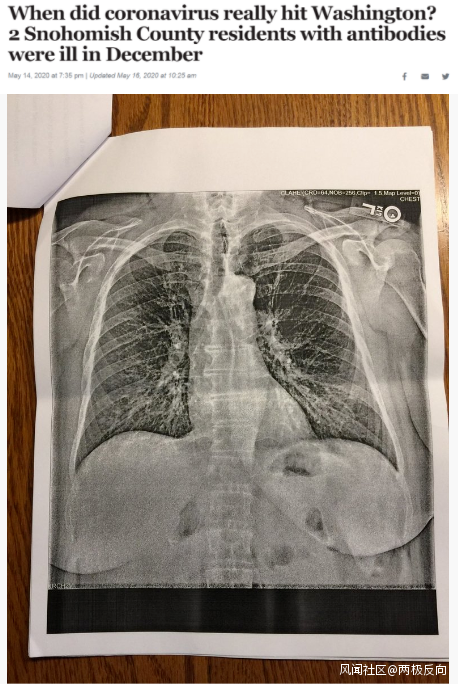

據《西雅圖時報》去年5月14日報道,華盛頓州斯諾霍米什縣的兩位居民在2019年12月出現類似新冠肺炎的症狀,之後對他們的新冠病毒抗體檢測呈陽性反應。這一結果表明,新冠病毒可能比想象中更早在當地出現。

△《西雅圖時報》報道截圖(題圖中的X光片顯示其中一位斯諾霍米什縣居民的肺部“過度充氣”並出現“線性混濁”。醫生認為,這可能是疊加上呼吸道肺部感染的表現。)